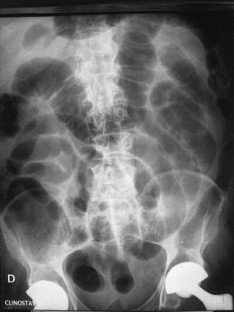

Fig. 1